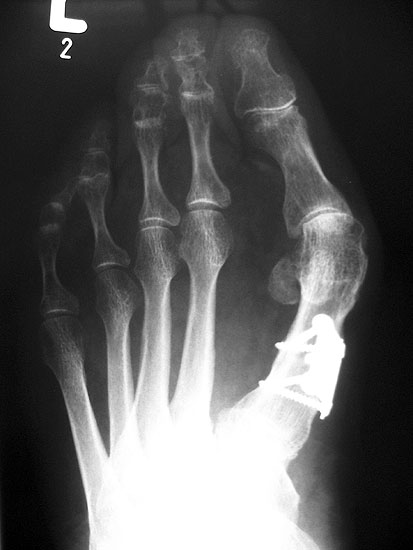

Die dorsoplantaren Röntgenaufnahmen zeigen eine Open-wedge Technik mit der normalerweise ein erhöhter intermetatarsaler Winkel gut zu korrigieren ist (Abbildung 3). Die Wirksamkeit einer Basisosteotomie ist umso größer, je proximaler diese durchgeführt wird. Je weiter distal die Osteotomie, umso geringer die Korrektur. Auf den postoperativen Bildern ist der distal unverändert große Abstand zwischen Metatarsale I und Metatarsale II erkennbar, bei gleichzeitiger Subluxation des Großzehengrundgelenks und dezentrierten Sesambeinen. Darüber hinaus finden sich initiale degenerative Veränderungen im Großzehengrundgelenk. Klinisch bestand eine hohe Weichteilspannung, bei verkürzter Extensor- und Flexor hallucis longus Sehne.  Daher wurde ein verkürzendes Verfahren zur Revision gewählt (Abbildung 4). Die Lapidusarthrodese stellt ein sehr zuverlässiges Verfahren zur Behandlung von Hallux valgus Rezidiven dar 9. Die Fusion des Tarsometatarsale-I-Gelenks kombiniert Stabilität mit einem hohen Korrekturpotenzial. Aufgrund der verfahrensimmanenten Verkürzung des ersten Strahls und der in diesem Fall bereits präoperativ vorhandenen Transfermetatarsalgie wurde die Entscheidung für eine verkürzte Weil-Osteotomie am zweiten bis fünften Strahl gefällt. Die Kombination beider Verfahren führte zu einem homogenen Metatarsale-Index und zu einer gleichmäßigen plantaren Druckverteilung 10. Die Hallux valgus interphalangeus Fehlstellung wurde mit einer Akin-Osteotomie korrigiert.